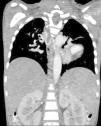

O cateterismo cardíaco confirmou a existência de colaterais com origem nos troncos supra‐aórticos, a ausência de artérias pulmonares centrais e a justaposição esquerda dos apêndices auriculares (Figura 2). A angiotomografia mostrou três major aortopulmonary collateral arteries (MAPCAs), destacou‐se uma com origem na vertente superior do arco aórtico, com estenose grave na sua origem e dilatação pós‐estenótica. Revelou ainda ausência de artérias pulmonares, comunicação interventricular de 25mm e normal drenagem das veias pulmonares na aurícula esquerda (Figura 3).